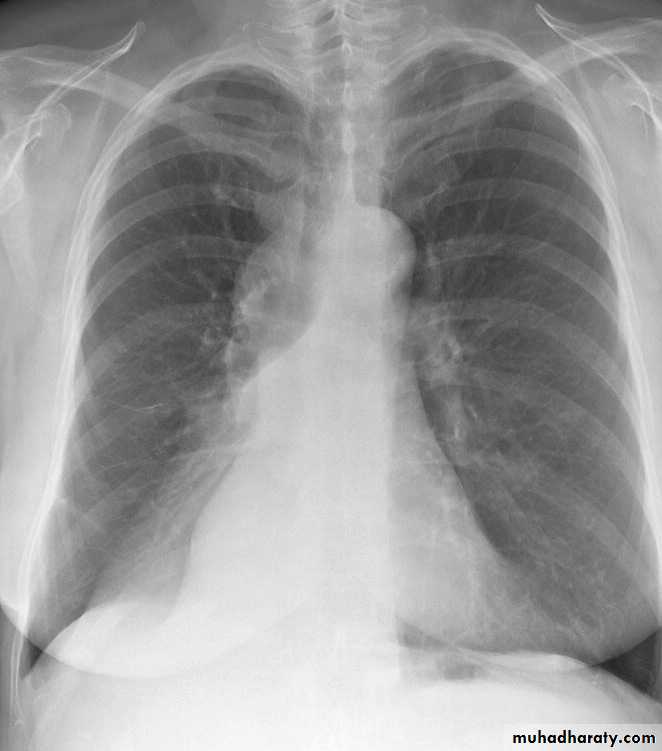

• Alveoiar oedema (‘Bat’s wings’)

• Kerlev B lines (interstitial oedema)

• Prominent upper lobe vessels

• Cardiomegaiy

• Pleura

• effusion

Kerley A lines (Arrows), Kerley B lines (arrowheads)